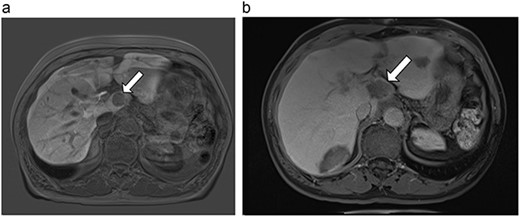

(a) Pre-ablation MRI demonstrating 15 mm lesion in caudate lobe of liver (image degraded by motion artifact). (b) Post-ablation MRI (20 days postoperatively) demonstrating 35 mm complete ablation of caudate lesion (image degraded by motion artifact).

| 2 (4a,b) | 67, M | Colon adenocarcinoma | 8 cycles capecitabine and oxaliplatin | 6 | Laparoscopic microwave ablation | 15 | 35 | 20 | 6 | No |